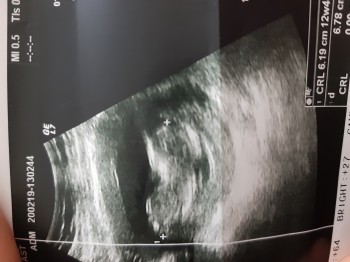

Bebeğim 12+1 haftalık

Bence kiz erkekte o kuyruk kismina dogru 30 derece bir egim gibi biswy oluyormus yukariya dogru sanki oyle okumustum seninki dumduz geliyor . Tabi bunlar dogruysa

Bende arkasını dönmüş büzmüş kendini diye pek anlayamadım ondan buraya attım canım:) bende öyle duymuştum 30 derece daha yukarda diye. Ama yan durmadığı için anlayamadım

bacakları toplu şekilde kıza benzettim.erkekler genelde ayakları yukarı doğru rahat uzatırlar.benim fikrim.rabbim gönlündekini nasip etsin.

bisey daha eklim bide kuyruk kısmı aşağı bakıyor kız gibi.hayirlisi olsun

Bence kiz canim. Erkek oldugunda 30 derece gibi bir egim oluyormus o kuyruk kismina dogru tabi dogruysa